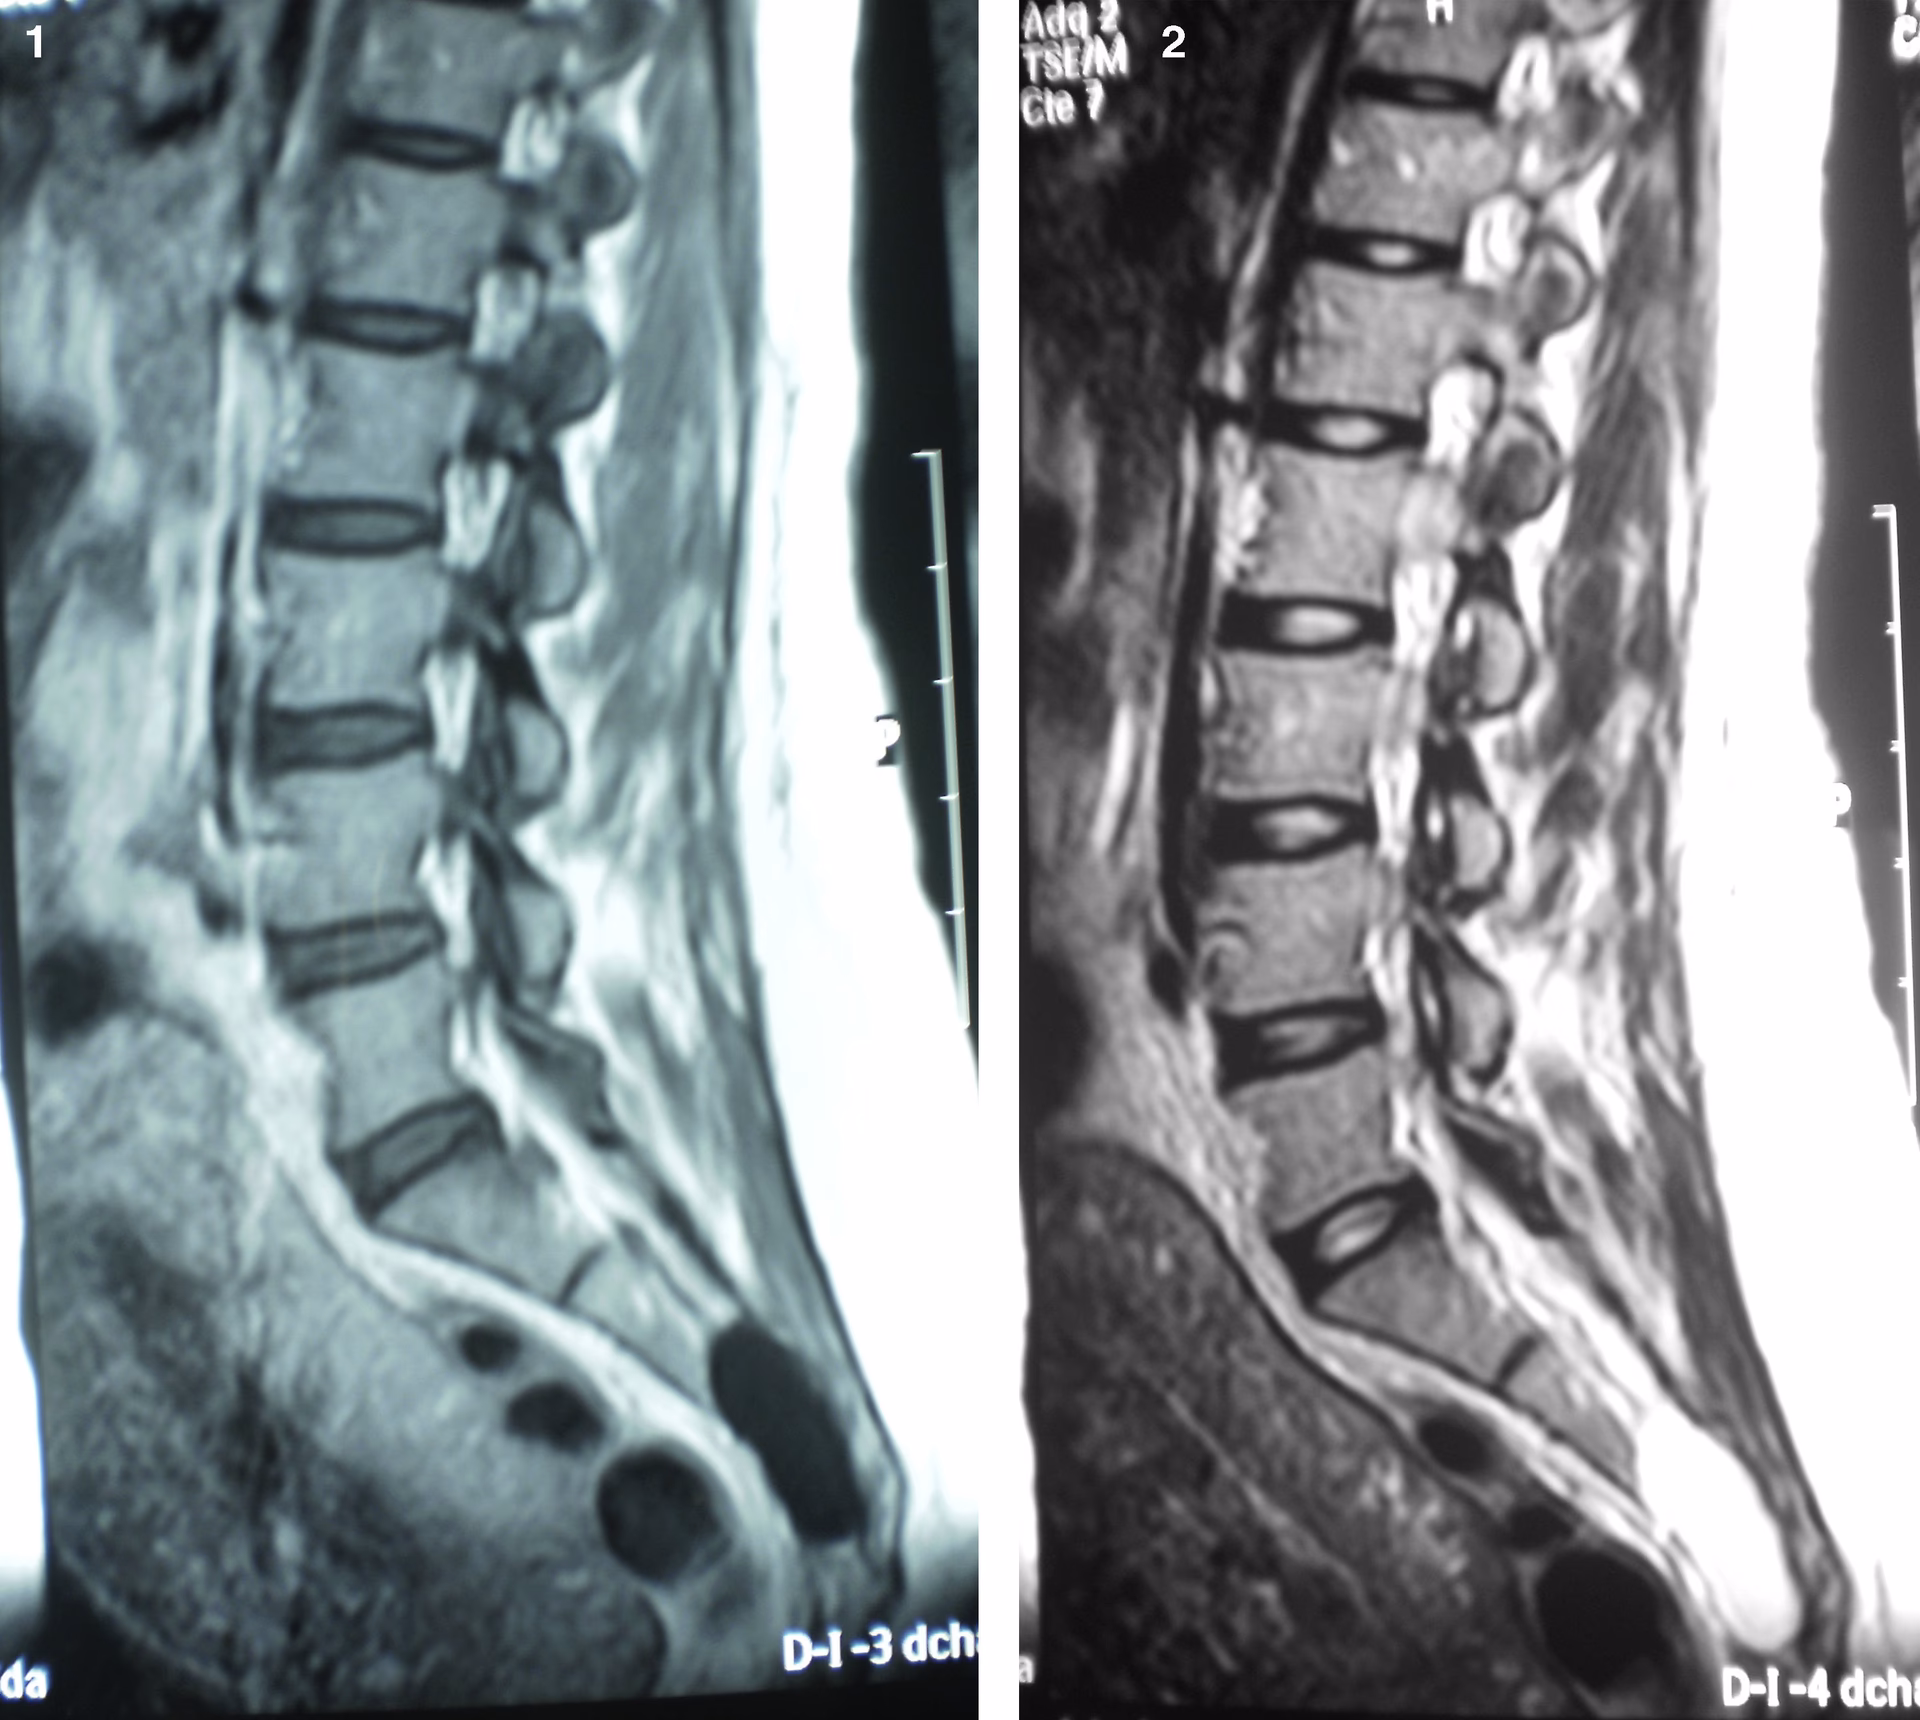

Descritos por primera vez en 1938 por el doctor Isadore Tarlov, estos quistes son sacos llenos de líquido cefalorraquídeo que se forman entre las capas más internas de las meninges (las membranas que cubren el cerebro y la médula espinal) a lo largo de la columna vertebral. Aunque pueden aparecer en cualquier nivel, son más comunes en la región sacra.

Se les conoce también como quistes perineuronales, perirradiculares o aracnoideos. La prevalencia de los Quistes de Tarlov se estima entre el 5% y el 13% de la población adulta, siendo más frecuentes en mujeres. A pesar de esta aparente frecuencia, la gran mayoría son asintomáticos y su descubrimiento suele ser casual, a menudo durante estudios de imagen realizados por otros motivos, como la búsqueda de la causa de un dolor lumbar inespecífico.